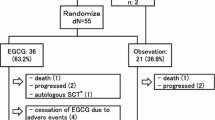

Of a total of 19 examined patients five patients were lost during the study period either due to death (n = 2), discontinuation of green tea consumption (n = 2), or heart transplantation (n = 1). All study patients (n = 14) were assessed by echocardiography. One patient died 1 month after study inclusion due to cardiac failure; the second death occurred after a 5-month stay at the intensive care unit with prolonged artificial ventilation, hemofiltration, recurrent infections, and finally death due to multi-organ failure after drainage of a retroperitoneal hematoma. Due to prior placement of cardiac pacemaker (n = 2), internal defibrillator (n = 1), orthopedic prosthesis (n = 1), or claustrophobia (n = 1) cMRI images were obtained only from 9 of the 14 study patients. The clinical state of the 14 study patients as well as oral heart failure medication remained unchanged during the observation period. None of the patients was hospitalized due to cardiac decompensation. The main clinical demographics of the 14 patients with 12-month follow-up are shown in Table 1. Detailed data for all 14 patients at the beginning and the end of the observation period are given in Table 1S (Supplemental information).